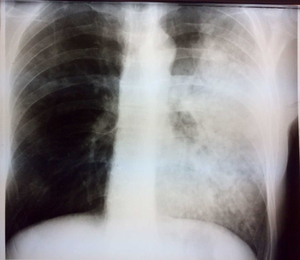

Barbat 45 de ani, fumator -20 / zi, tuşitor, sputa mucoasa, fara dispnee

SaO2 = 90%; TA = 120 / 80mmHg; puls = 101 / min; stetacustic nimic; VSH normal,; PCR = normal; fibrinogen = 360 mg%;

CT TORAX NATIV: focar de umplere alveolară cu bronșigramă aeriană care interesează aproape întreg lobul stâ